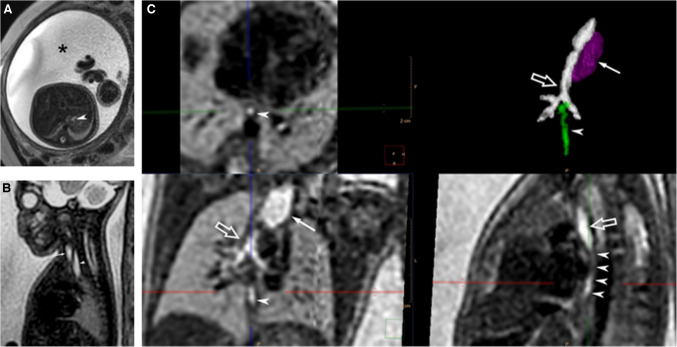

背景:食管闭锁的产前诊断仍然具有挑战性,羊水过多、胃泡小或不存在、食管上袋扩张等间接体征经常不一致地出现。只有10-40%的EA病例是产前诊断出来的。胎儿MRI可以克服超声的限制;然而,运动等限制因素会阻碍对食道的评估。方法:采用切片-体积重构(SVR)技术进行超分辨率成像是提高图像质量的一种方法。该技术从标准的胎儿MRI切片生成高分辨率3D图像,以提高诊断准确性。目的:应用SVR超分辨率成像技术对气管食管瘘进行准确诊断和诊断。结论:该技术在准确描绘相关手术解剖结构方面具有重要潜力,可改善手术计划。

Background: Prenatal diagnosis of esophageal atresia remains challenging, with indirect signs such as polyhydramnios, a small or absent stomach bubble, and a dilated upper esophageal pouch often inconsistently present. Only 10-40% of EA cases are diagnosed prenatally. Fetal MRI can overcome ultrasound limitations; however, constraints like motion can hinder evaluation of the esophagus.

Methods: Super-resolution imaging with slice-to-volume reconstruction (SVR) is one approach that can improve image quality. This technique generates high-resolution 3D images from standard fetal MRI slices to enhance diagnostic accuracy.

Aim: We present the application of super-resolution imaging with SVR to accurately diagnose EA and assess the presence or absence tracheoesophageal fistulas.

Conclusion: This technique demonstrates significant potential for accurately delineating the relevant surgical anatomy, which can improve surgical planning.